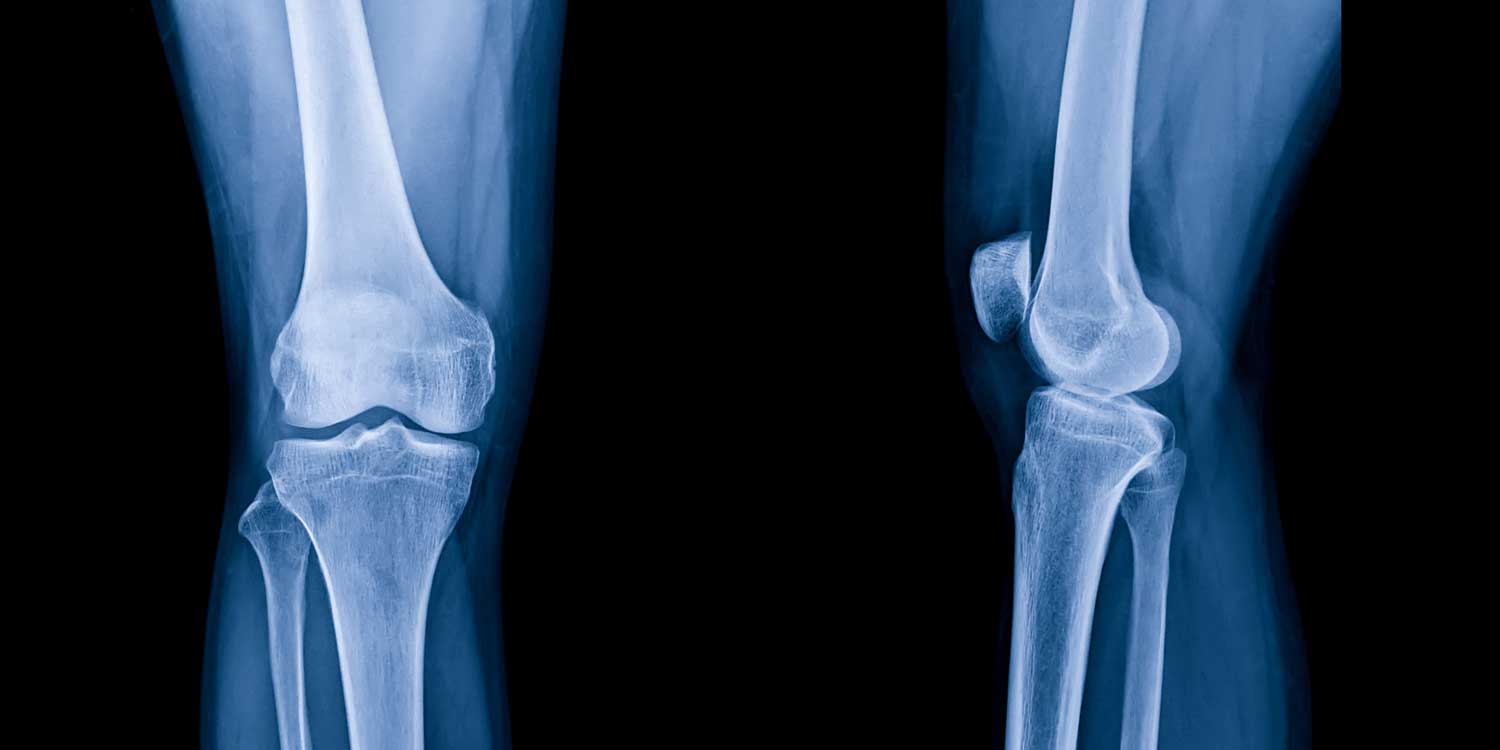

Osteoarthritis is a degenerative condition in which the cartilage cushioning the joint surfaces gradually breaks down over time. Because cartilage is not visible on X-ray, its loss is assessed indirectly by the space between the bones. As cartilage wears away, the gap between the femur (thighbone) and tibia (shinbone) narrows — and eventually disappears entirely in severe disease, producing bone-on-bone contact. A knee X-ray reveals four classic hallmarks of this process.

Joint space narrowing is the primary marker of cartilage loss. Radiologists assess the joint space in each of the three knee compartments: the medial (inner) compartment between the femur and tibia on the inside of the knee (the most commonly affected area), the lateral (outer) compartment, and the patellofemoral compartment between the kneecap and the front of the femur. Weight-bearing X-rays are essential here — non-weight-bearing images can make arthritic joints look better than they are, as the normal load on the knee is what drives the bones together and reveals the true extent of cartilage loss.

Osteophytes (bone spurs) are bony projections that form at the margins of the joint surfaces and the attachment points of ligaments and tendons as the body attempts to stabilize a worn joint. Osteophytes are a hallmark of OA and become more prominent as the disease advances. They can sometimes cause mechanical symptoms — catching, locking, or restricted range of motion — if they grow large enough to interfere with joint movement.

Subchondral sclerosis is increased density (whitening) of the bone just beneath the joint surface. When cartilage is lost, the underlying bone absorbs more compressive load than it was designed to, and it responds by becoming denser. This appears as a bright white band running along the joint surface on the X-ray.

Subchondral cysts are small fluid-filled cavities that form in the bone beneath the arthritic joint surface. They appear as small round lucent (dark) areas just below the dense white sclerotic band and indicate significant joint loading and bone remodeling.

In advanced disease, the joint may show malalignment as well — varus deformity (“bowlegged”) from medial compartment collapse, or valgus deformity (“knock-kneed”) from lateral compartment collapse. These alignment changes are visible on the standing AP view and have important implications for surgical planning.

A weight-bearing AP knee X-ray shows the medial and lateral tibiofemoral compartments under real physiological load — the most accurate view for assessing joint space narrowing and assigning a Kellgren-Lawrence grade.